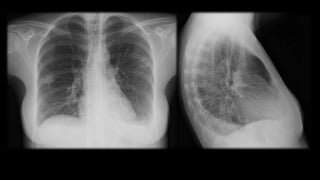

Una mujer de 31 años fue ingresada por faringoamigdalitis pultácea que no mejoró con tratamiento ambulatorio. Presentaba también molestias abdominales, náuseas, vómitos y diarrea. Las pruebas revelaron anemia grave, hipertransaminasemia e infiltrados pulmonares. El diagnóstico final fue bacteriemia por Fusobacterium necrophorum, trombosis de la vena yugular interna izquierda e infiltrados pulmonares, confirmando el síndrome de Lemierre.